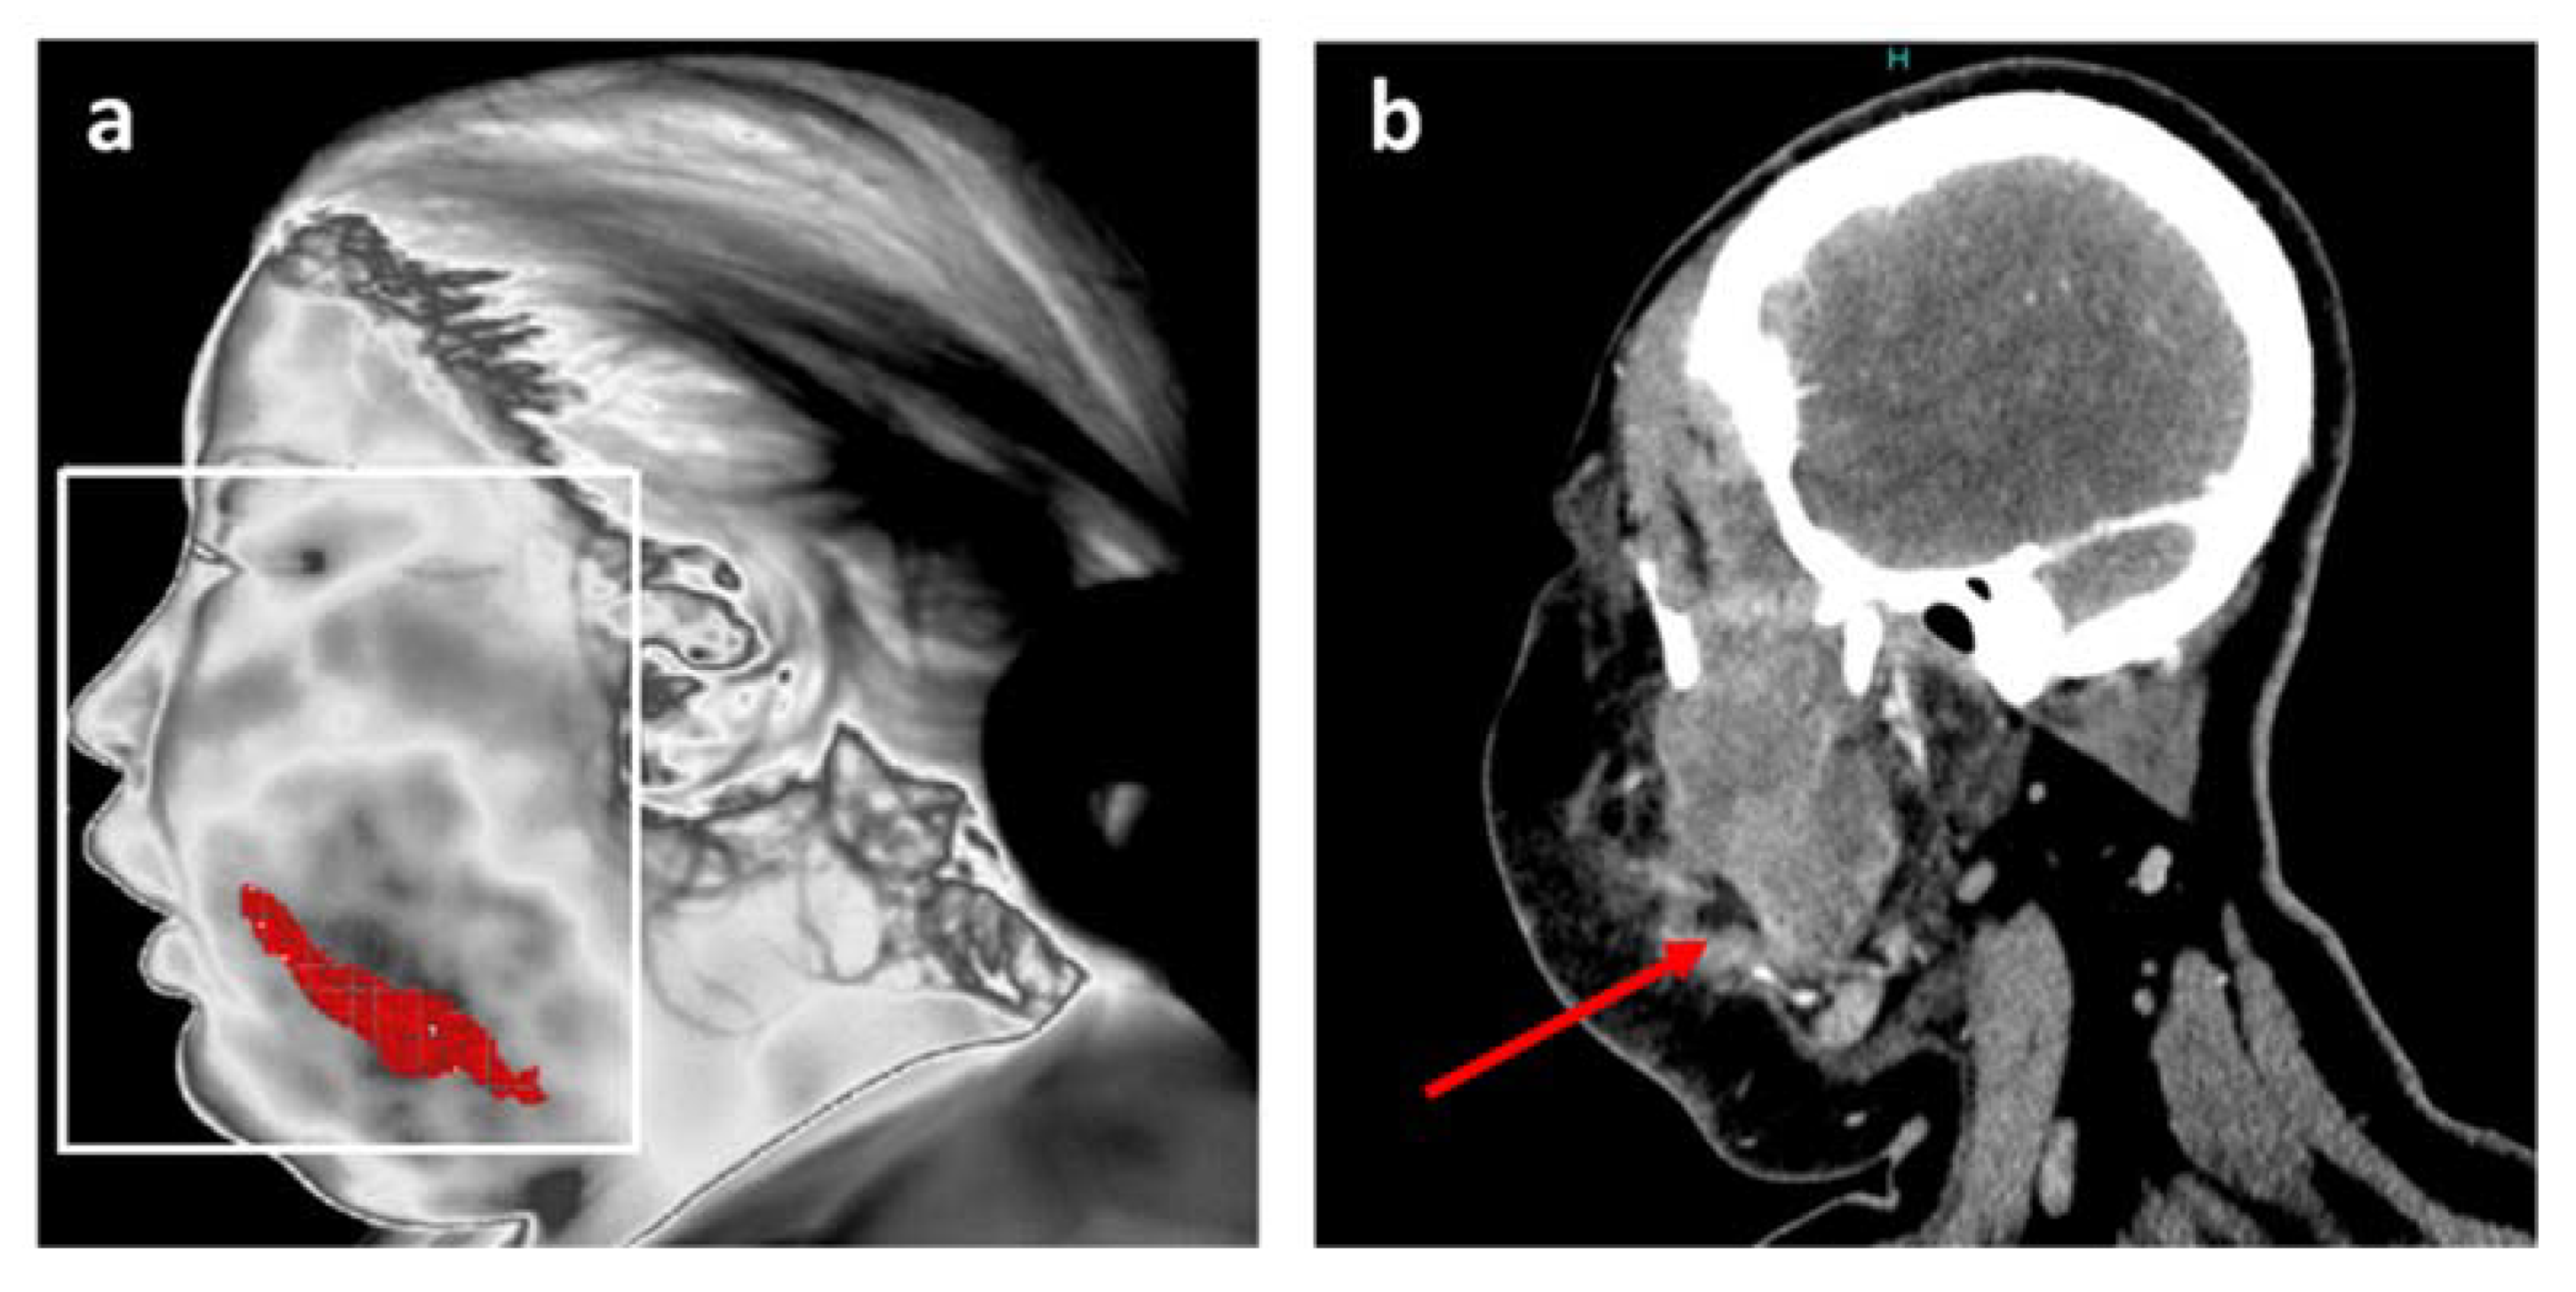

One of the original features of the adopted approach consists of its ability to reposition the inflamed areas detected on patients’ faces. The final result is shown in Figure 3a. Finally, thermal image processing confirmed that infection was limited to the buccal space without reaching any danger zone such as the eye or a more posterior zone such as around the pharyngeal axis.

Figure 3.

Position of the main inflammation site after thermal analysis for patient 1. (a) Resulting accurate localization of main inflammation linked to facial cellulitis with MIT; (b) Coronal plane of CT scan in soft tissue window at the level of the infectious collection (red arrow).

This information is in agreement with the data from the head and neck CT scan, and is notably comparable with a CT image in a coronal plane at the level of the infectious collection (Figure 3b).